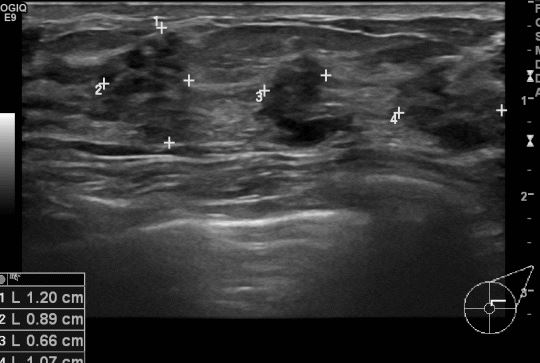

건진상 이상소견 있어  타원에서 좌측유방2시 방향으로 조직검사 실시후 양성소견진단받고 내원한 40세 여자환자분으로 본원에서 맘모톰 실시후 침윤성유관암진단되셨습니다.